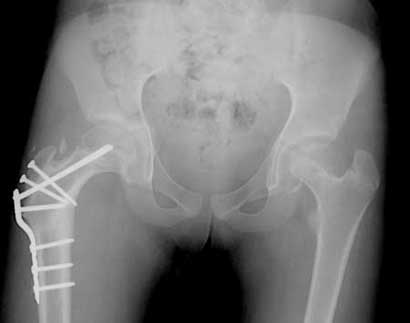

Bilateral caput valgum correction

Bilateral caput valgum – correction with Wagner type of varus and neck lengthening osteotomy on the right for a similar deformity as seen on the left.